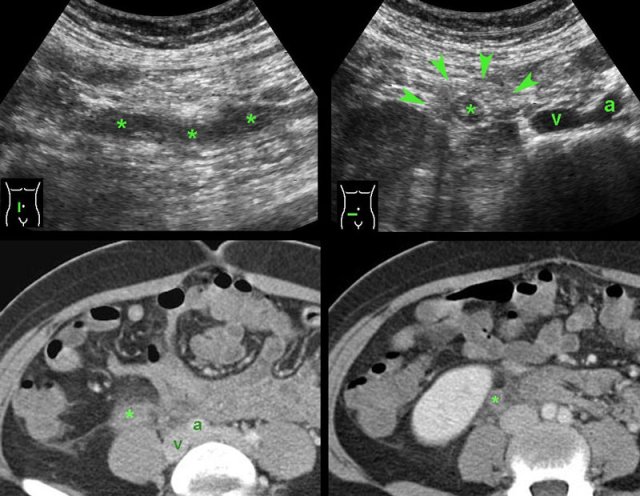

case 1

Four days after delivery this young woman developed

pain in the RLQ and a CRP of 125.

At the spot of maximum pain an ill-defined, solid,

tubular, hypoechoic structure (*) was seen, surrounded by hyperechoic, non-compressible,

inflamed fat (arrowheads).

CT confirmed an ovarian vein thrombosis. The surrounding

fat-stranding suggested a concomitant, phlebitis-component.

Complete recovery with antibiotics and anticoagulant therapy.

case 2

This patient presented with RLQ pain 5 days after the procedure.

US demonstrated a thrombus in the right ovarian vein, there was no clear phlebitis

component.

CT confirmed a thrombus in the right ovarian vein, without

any fat stranding.

CRP remained low.

Complete cure with only anticoagulant therapy.